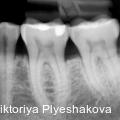

Nichtchirurgische Therapie tiefer PA-Defekte mit NaOCl-Gel und vernetzter Hyaluronsäure